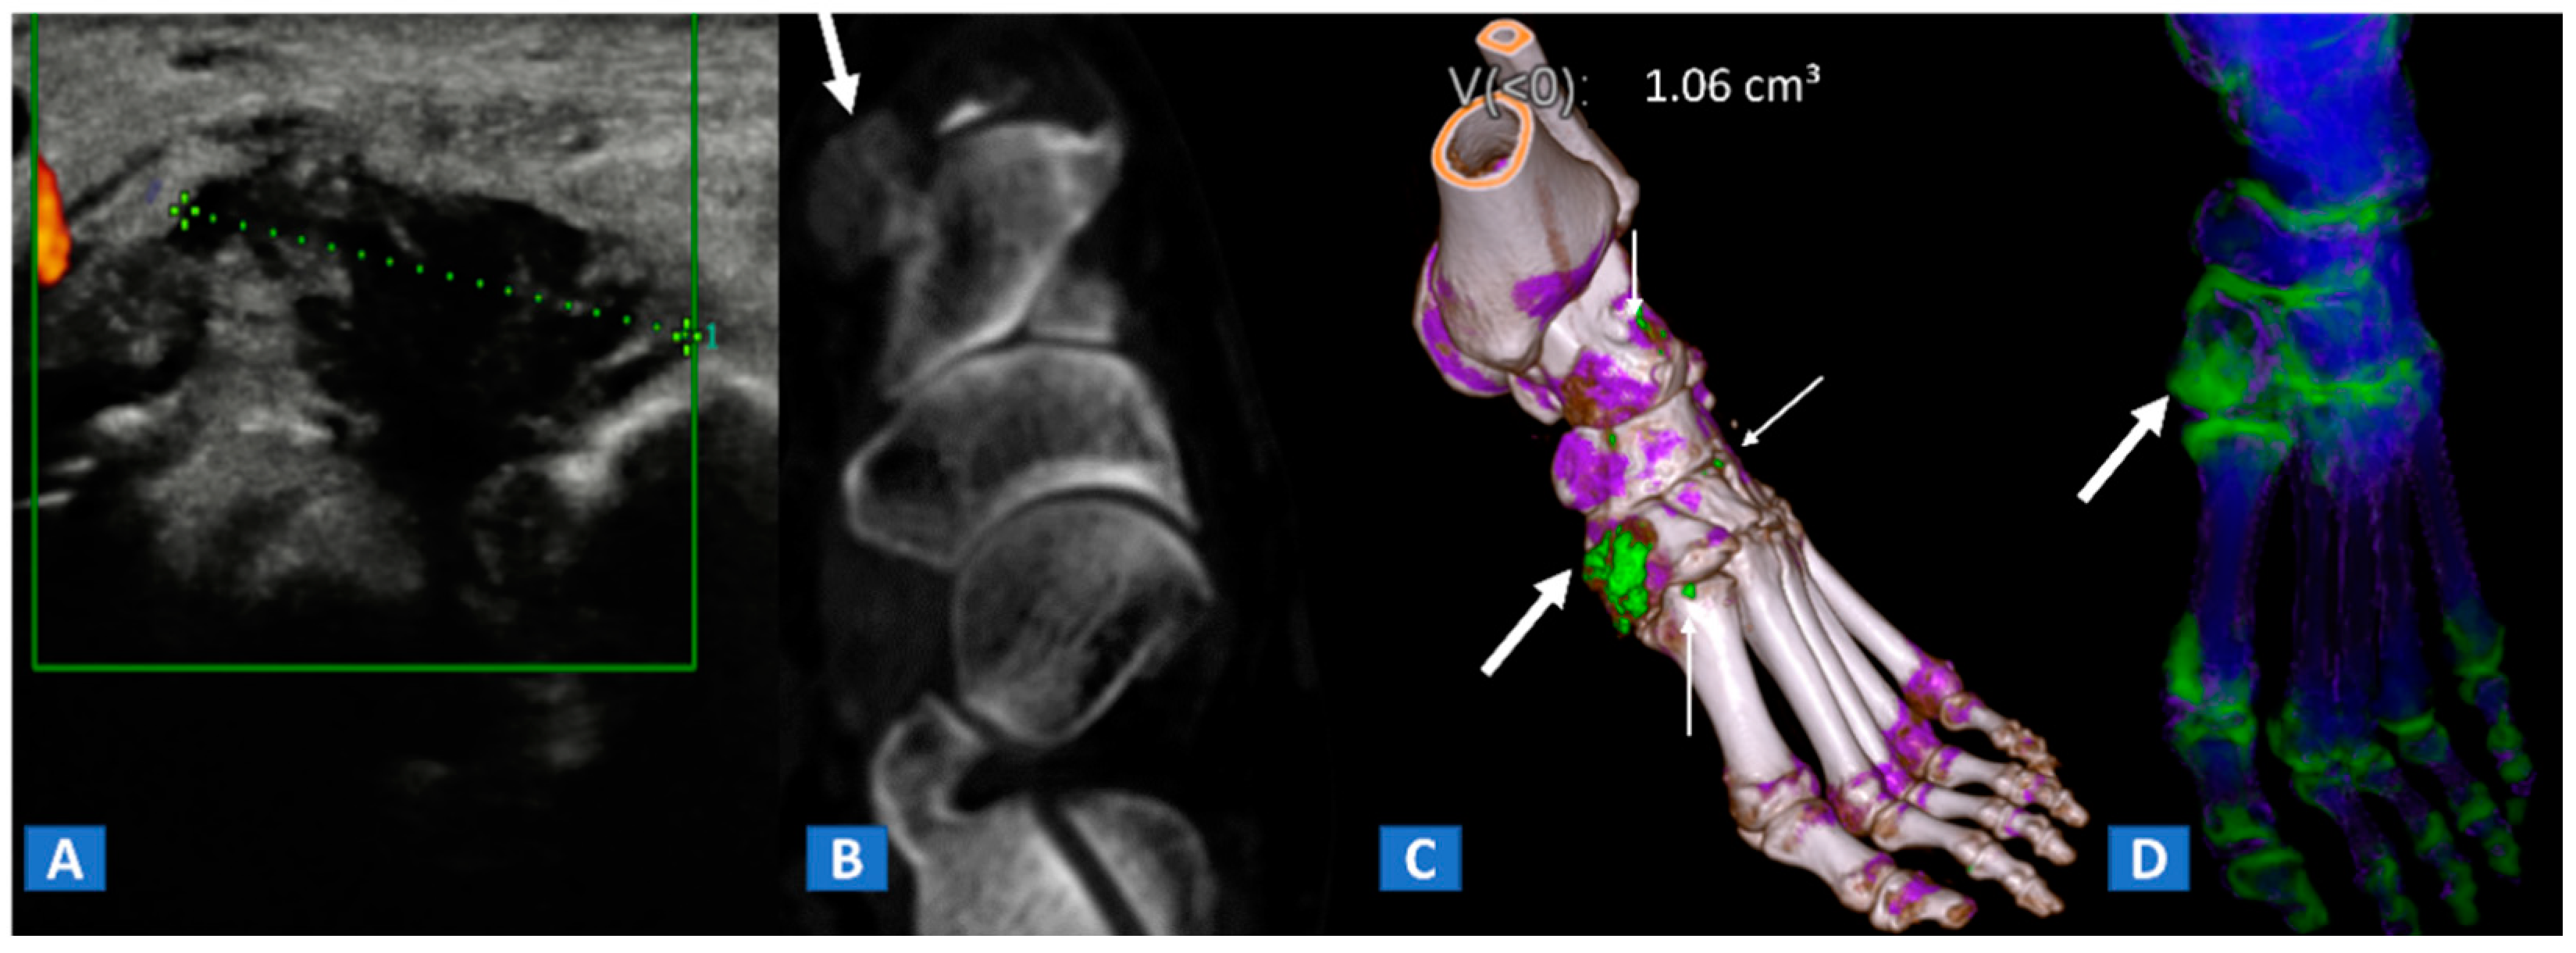

Figure 9.

A 48-year-old female with painful gout. Upon ultrasound study, a hypoechoic tophus is identifiable (A). In the axial CT image with soft-tissue window (B), the tophus shows soft-tissue density (arrow). On the 3D DECT image for gout analysis (C), the tophus is coded in green (thick arrow). Note the presence of tiny additional tophi (thin arrows). On the DECT 3D map (D), BME can be identified on the intermediate cuneiform and on the base of the first metatarsal bone; this may be an additional factor contributing to pain.